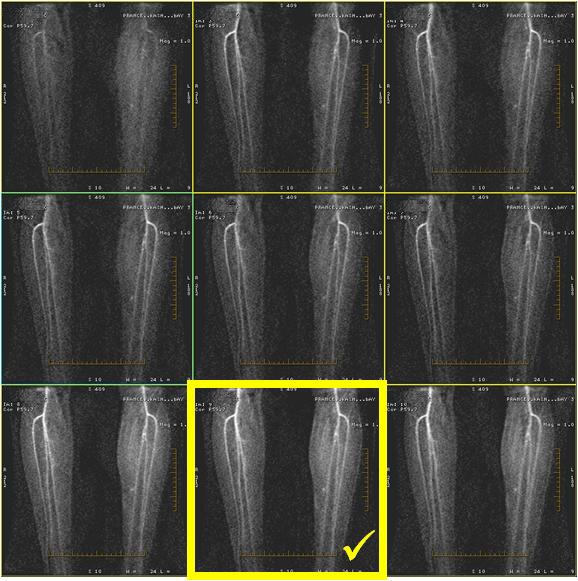

- Diastolic Trigger Delay: View the multi-phase SSFSE images from the Viewer. Select the Trigger Delay based on the image that displays conspicuous arterial signal, the sharpest vessels, and 1-2 phases before any blurring/ghosting occurs. The Trigger Delay is displayed in the Patient List. Enter this value on the Cardiac tab. Use Recommended Delay if a multi-phase SSFSE scan was not acquired.

Figure 3. Multi-phase SSFSE image outline in yellow best demonstrates vessels of interest